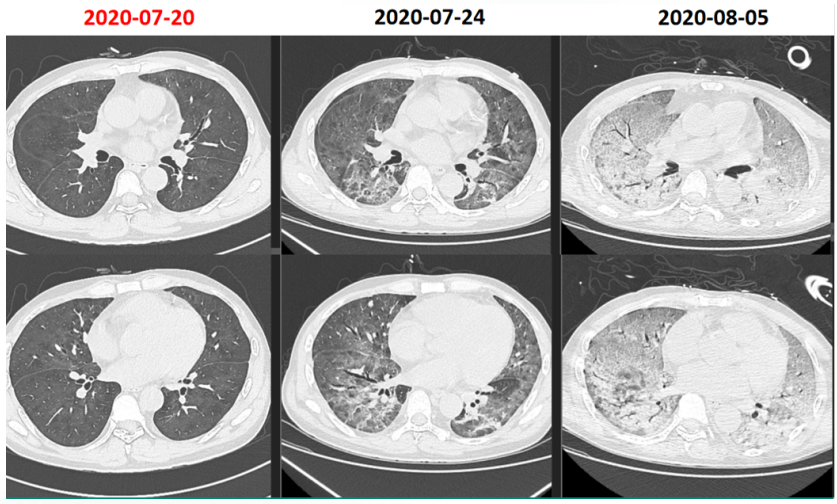

病例2:肾移植术后半年,发热3天。影像学表现并不严重(图10)。入院后完善NGS,耶氏肺孢子菌序列数330000。入院后即予SMZ+卡泊芬净+甲泼尼龙治疗,但病情仍然加重,入院10天转ICU,影像学持续进展(图11)。患者入ICU后NGS结果回报耶氏肺孢子菌序列数843433周后死亡。

图片

10  患者入院胸部CT

11  患者病程中胸部CT变化情况

文献报道,SMZ可以结合二氢叶酸合成酶(DHPS)基因位点从而抑制DHPS的合成TMP可以结合二氢叶酸还原酶(DHFR)基因位点从而抑制DHFR的合成达到杀灭耶氏肺孢子菌的作用国外学者1998年即发现了耶氏肺孢子菌DHPS基因突变,且接受磺胺及氨苯砜预防患者突率远高于未预防患者(70.6%:16.6%);Van Hal等发现DHPS基因型密码子55和57突变与疾病严重程度相关,与野生型相比,患者有创通气的比例更高,且临床结局更差。这一案例提醒我们,对于SMZ治疗效果不佳的患者,应及时进行BALF二次送检,若耶氏肺孢子菌丰度值依然较高,需警惕磺胺耐药的发生,及时更换治疗方案